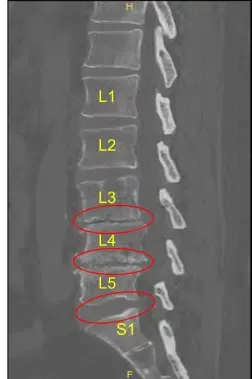

La resonancia magnética y la tomografía computarizada de la columna lumbar mostraron una grave ruptura degenerativa del espacio discal en L3-L4 y L4-L5, por lo que se les ofreció una cirugía para el dolor discogénico. Se explicaron extensamente los riesgos y posibles beneficios de la cirugía al paciente.

El espacio del disco se estrecha en L3-L4 y L4-L5

Protuberancia discal y artropatía facetaria

Firmaron el consentimiento informado y fueron llevados al quirófano para el procedimiento mencionado. Los hallazgos de la radiografía preoperatoria de la columna lumbar se muestran arriba y los pacientes también se sometieron a una tomografía computarizada preoperatoria (TAC) que se muestra arriba.